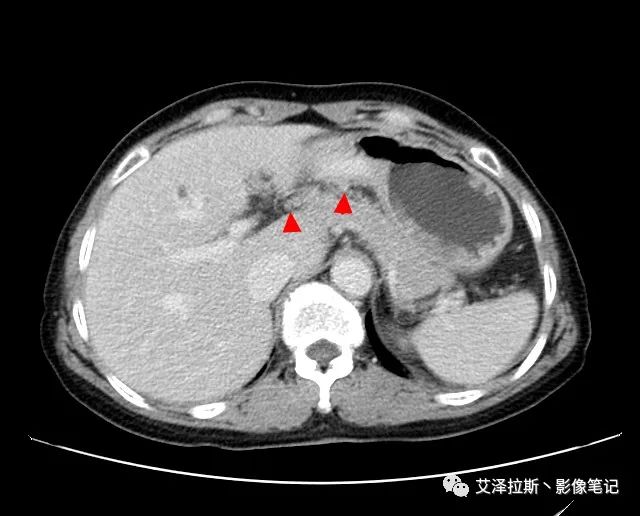

【基本情況】 患者,女性,66歲,貧血。

圖1 平掃+增強各期

【影像所見】 胃竇部狹窄,胃壁環形增厚,小彎側見一巨大潰瘍,周圍伴“環堤征”,漿膜面不完整,胃周脂肪見網格狀條索影,病灶與肝臟左葉、胰腺鉤突脂肪間隙消失,增強掃描病灶明顯強化。引流區內約15個區域淋巴結受累。

【診斷意見】 胃竇部胃癌(T4N3期) 該病例腫塊突破漿膜層,與肝臟左葉、胰腺鉤突分界不清,脂肪界面消失,定為T4期; 受累及的淋巴結為15個區域,定為N3; 有無遠處轉移尚不明確,所以M期暫時無法確定。